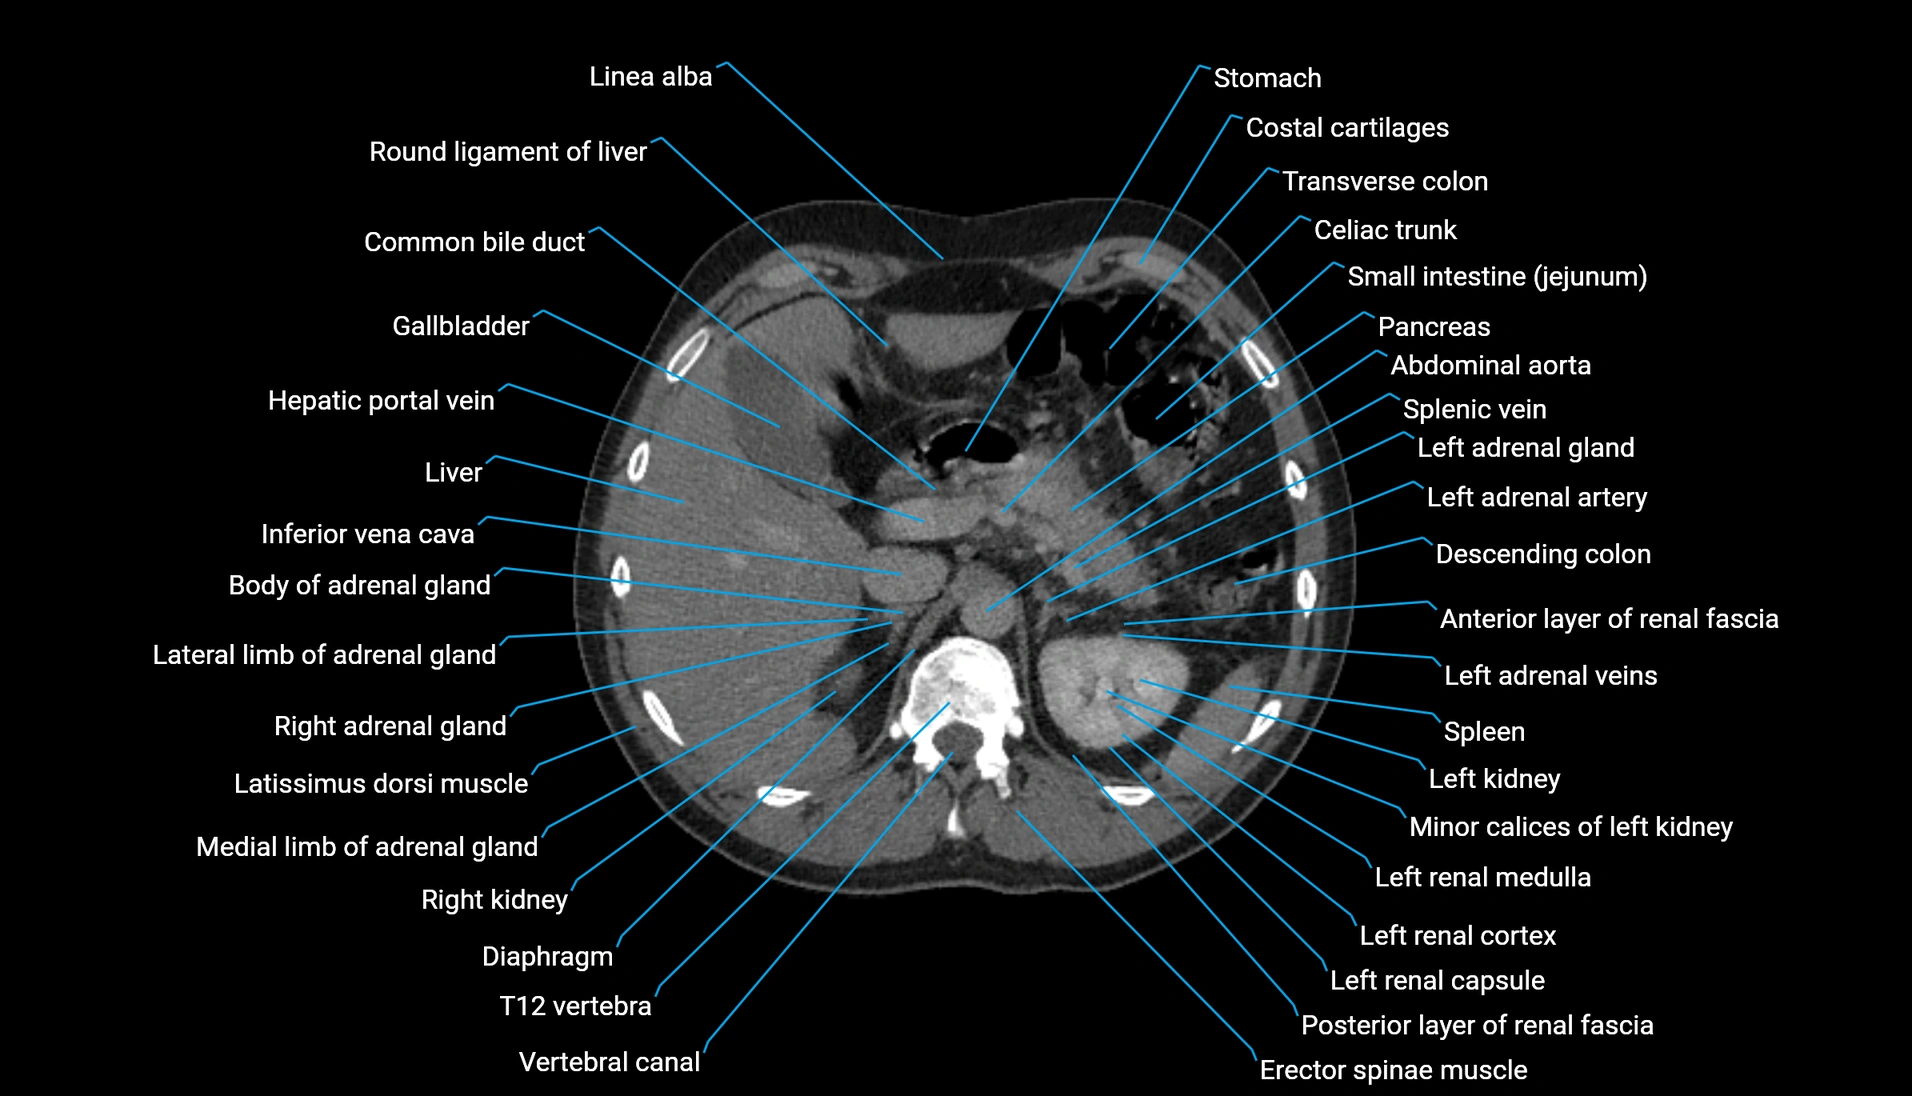

CT Appearance

Non-contrast CT:

-

Demonstrates cortical bone of acetabular rim in excellent detail

Detects fractures, dysplasia, retroversion, or bony overcoverage (pincer impingement)

3D reconstructions used in preoperative hip surgery planning

CT VRT 3D image

CT image